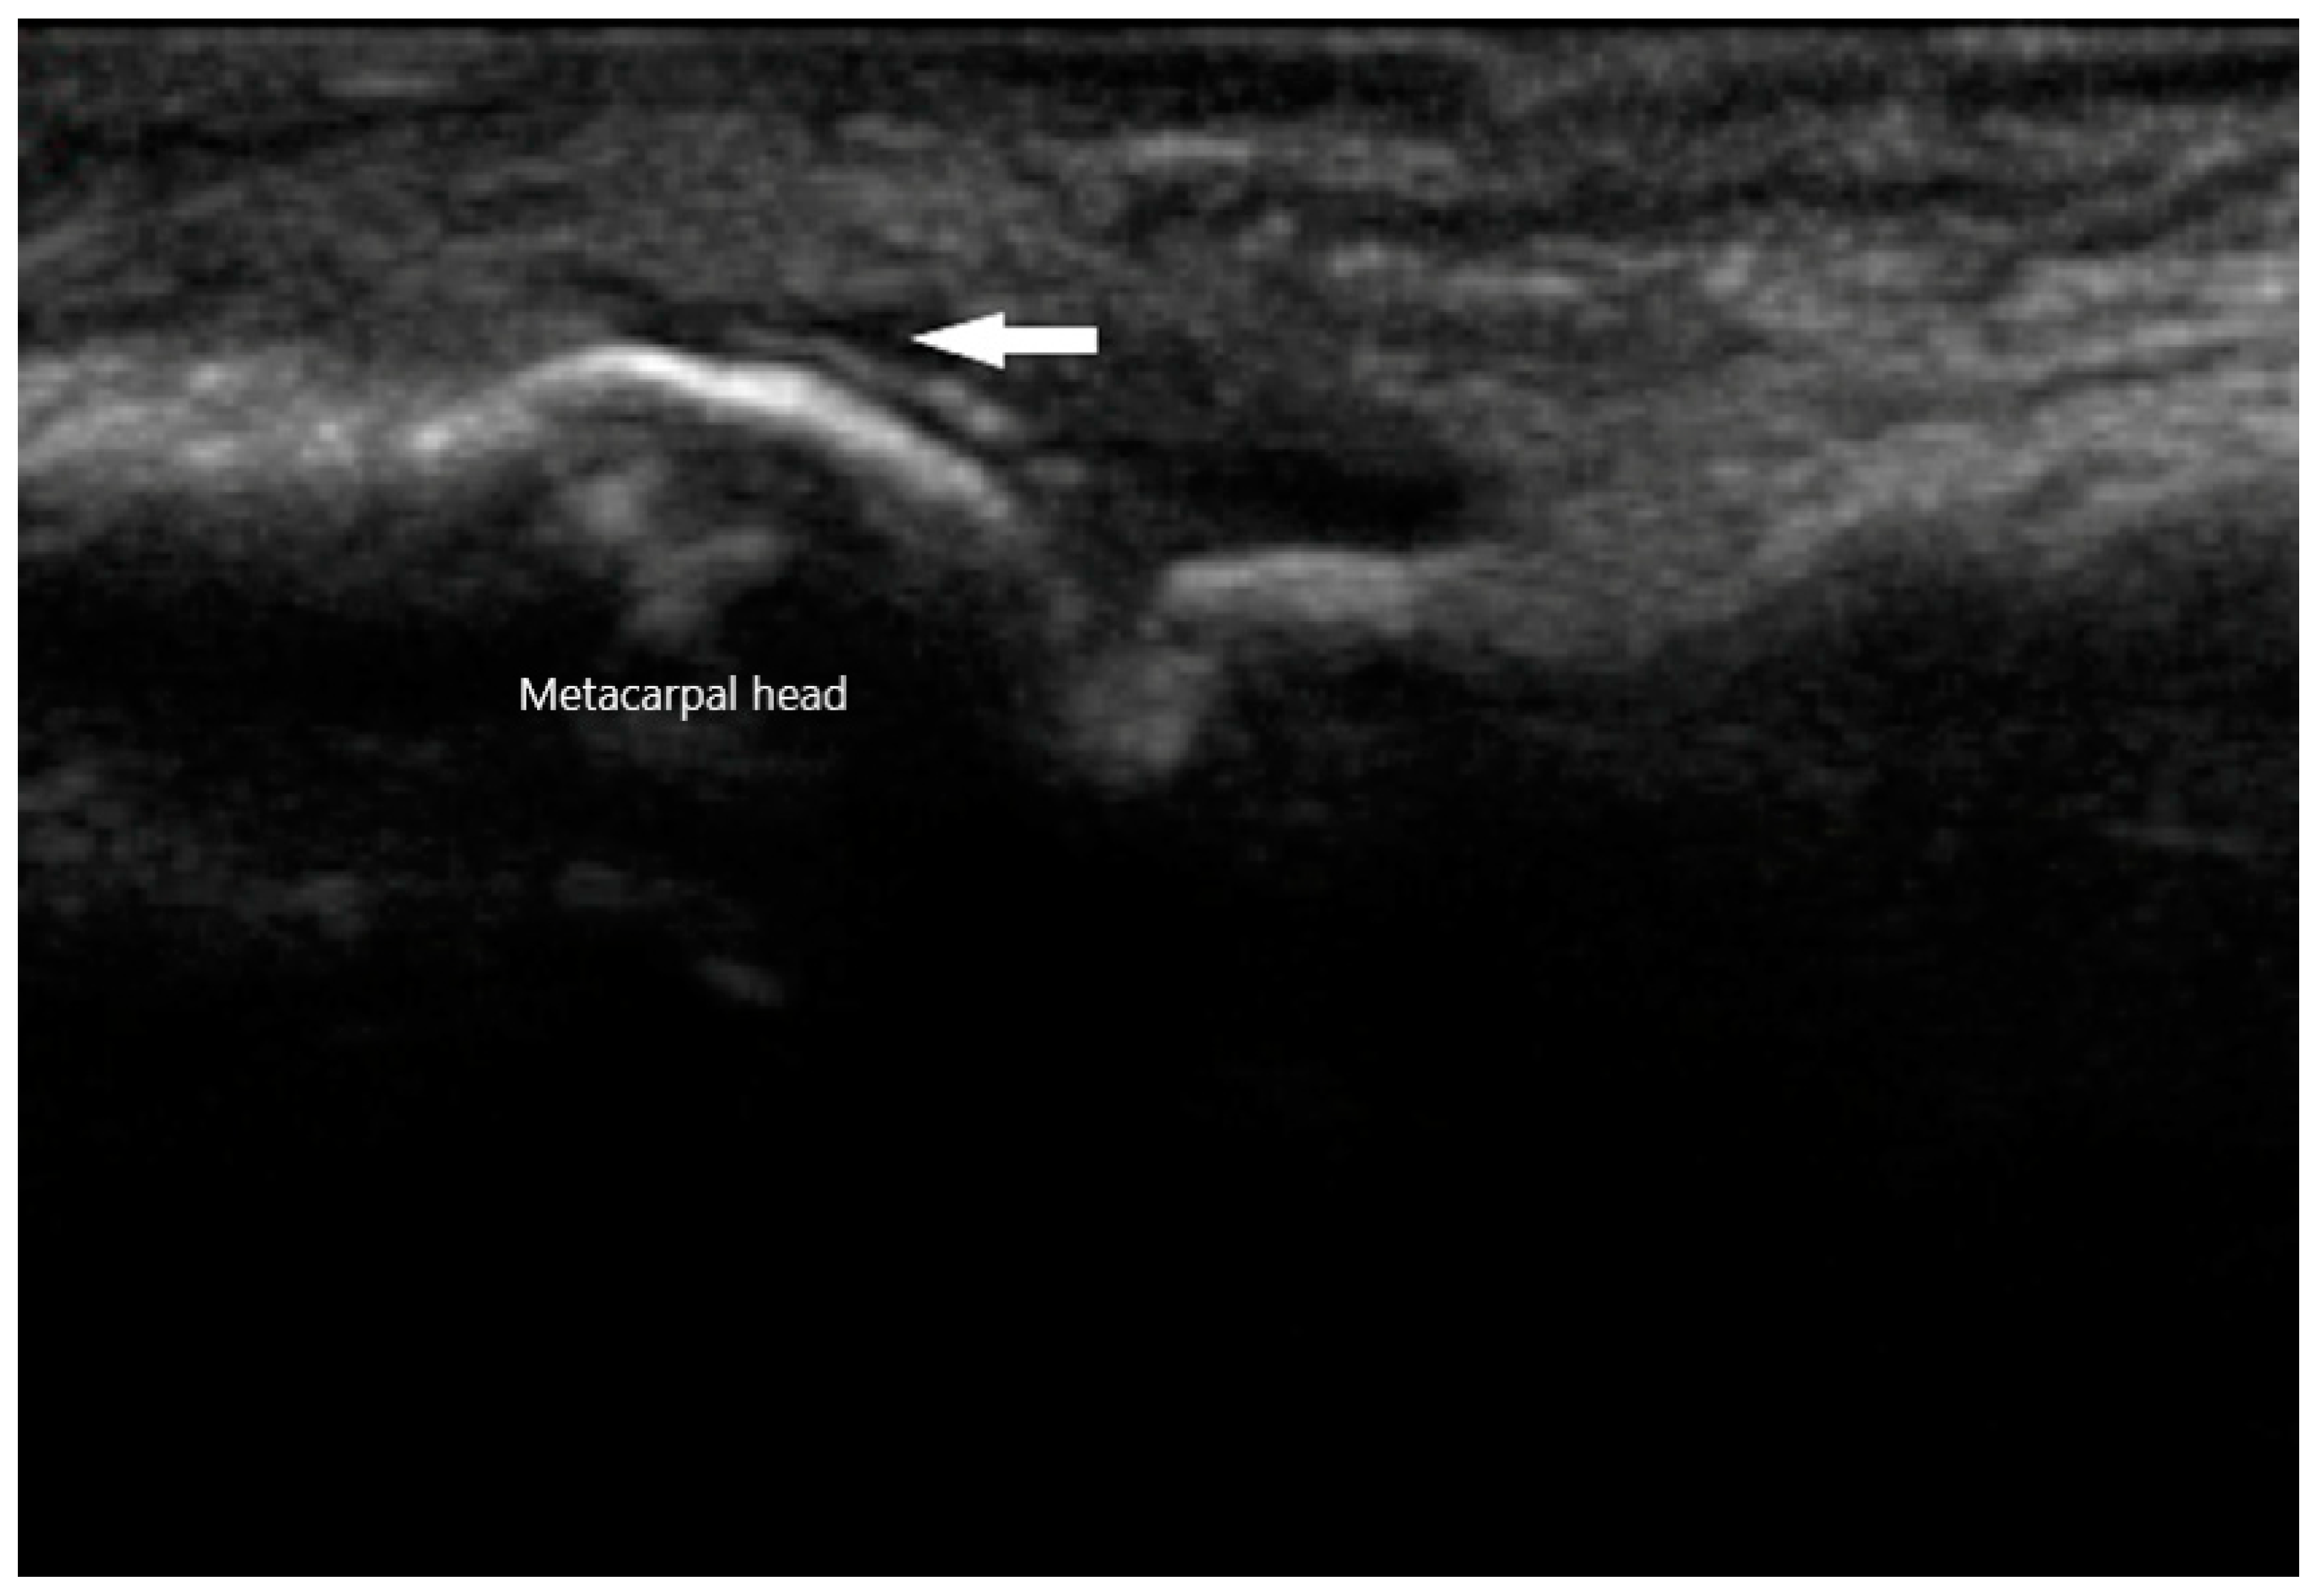

MSU crystals can be seen easily via US as they reflect US waves. They typically appear to be hyperechoic on the superficial margin of the cartilage in either a homogenous or irregular distribution, typically referred to as a “double contour” sign [53] (Figure 9). Any joint can exhibit this finding, but it is most commonly seen in the suprapatellar short axis view of the knee when placed in a flexed position. This ultrasonographic finding is highly suggestive of gout, with a specificity of 97.3% and a positive predictive value of 93.3%. The sensitivity and negative predictive value, on the other hand, is low at 36.8% and 60% respectively [54]. When using the “double contour” sign, one common pitfall is the occasional smooth, hyperechoic appearance of the surface of hyaline cartilage. While it may appear as a “double contour”, only the part of the cartilage that is perpendicular to the US beam will be visible. In contrast, MSU deposition exhibits a more diffuse and irregular pattern. Gouty bone erosions are more effectively detected via US compared to plain radiographs, with respective rates of 67% and 28% for the first metatarsal phalangeal joint [55].

Figure 9. Double contour sign (arrow) of metacarpal head in gout.